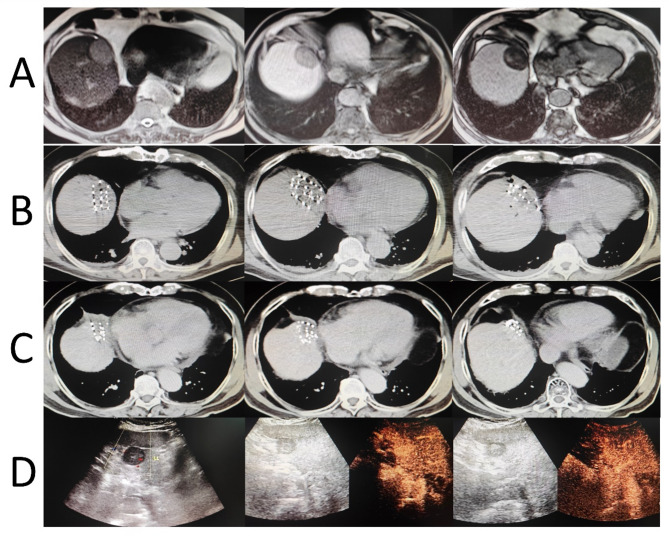

Methods: A retrospective analysis of 71 patients (57 males, 14 females, median age 64) treated at three Chinese hospitals from 2018 to 2024 was conducted. The main outcomes were local progression-free survival (LPFS) and overall survival (OS). Treatment involved a 16-slice Spiral CT and Radioactive Particle Treatment Planning System (TPS), with seeds of 18.5-29.6 MBq implanted via freehand puncture. Efficacy was evaluated using the modified Response Evaluation Criteria in Solid Tumors (mRECIST) at three months, with follow-ups every three months for three years, then biannually until December 2024. Data analysis utilized SPSS 22.0, Kaplan-Meier, and Cox models.

Results: With a median follow-up of 37 months, the complete response (CR) rate was 57.7%, partial response (PR) 31.0%, stable disease (SD) 5.6%, and progressive disease (PD) 5.6%. Local control was 94.3%. LPFS rates at 1, 3, and 5 years were 74.6%, 29.5%, and 1.4% (median LPFS 22 months), while overall survival (OS) rates were 88.7%, 47.8%, and 12.6% (median OS 35 months). CR was a key protective factor for LPFS and OS. Significant factors included the Barcelona Clinic Liver Cancer (BCLC) stage C, intrahepatic progression, and extrahepatic metastasis. Postoperative complications occurred in 35.2% of patients, with no severe cases.